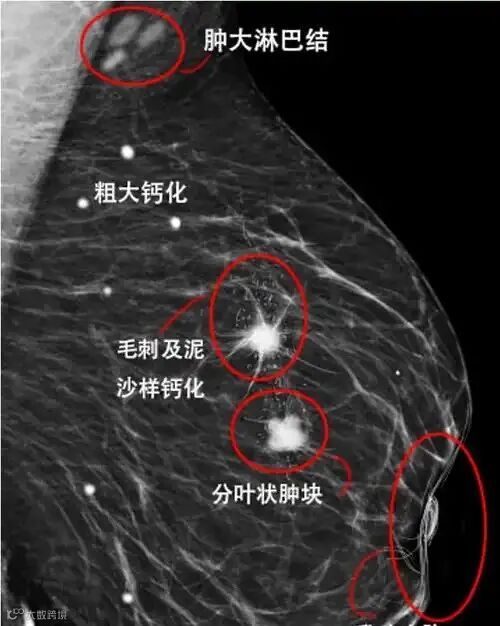

为突破CNN在建模长距离依赖上的局限性,Transformer架构被引入医学影像分析领域。Vision Transformer(ViT)将图像划分为patch序列,通过自注意力机制建立全局关联。Qwen系统采用Swin Transformer作为主干,其滑动窗口机制有效降低了计算复杂度,适配高分辨率医学图像。在乳腺钼靶BI-RADS分级任务中,基于Swin Transformer的模型在CBIS-DDSM数据集上的分类准确率达到86.5%,尤其在疑难病例的判别上展现出优势。

乳腺钼靶图像分析是AI的另一重要应用场景。乳腺癌是女性最常见的恶性肿瘤,数字乳腺X线摄影仍是大规模筛查的主要工具-1。其中,微钙化群往往是导管原位癌的重要征象,但因其尺寸小(0.1–1mm)、分布散在,极易被忽略-1。Qwen系统采用两级检测架构应对这一挑战:第一级使用RetinaNet-like目标检测器识别潜在钙化点;第二级通过图神经网络建模空间聚集模式,判断其形态学特征是否符合恶性倾向-6。关键技术包括ROI自适应增强(采用CLAHE提升局部对比度)、多视图融合(整合MLO与CC双视角信息)以及BI-RADS自动建议。日本的一项大规模多机构临床试验显示,基于SE-ResNet模块的AI系统在乳腺癌诊断中达到83.5%的敏感度和84.7%的特异性,AUC为0.841。